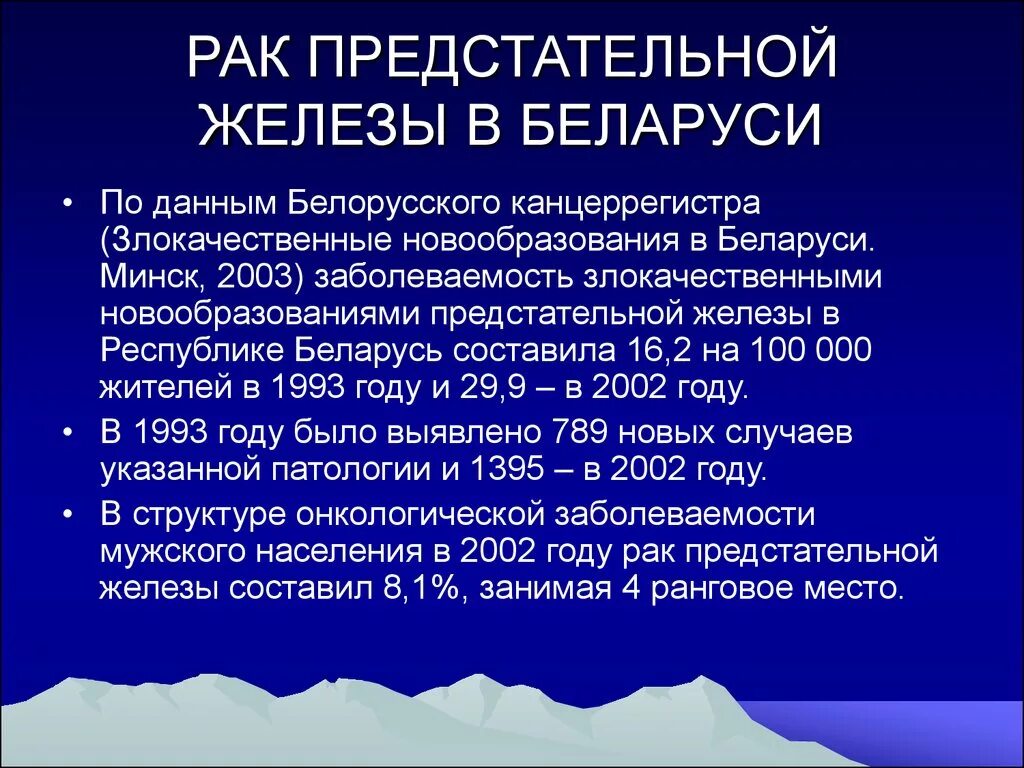

Опухоль предстательной железы. Карцинома предстательной железы. Опухоль предстательной железы презентация. Онкология предстательной железы

Опухоль предстательной железы. Карцинома предстательной железы. Опухоль предстательной железы презентация. Онкология предстательной железы Опухоль предстательной железы. Злокачественная опухоль предстательной железы. Карцинома предстательной железы. Предстательная железа развивается из

Онкология предстательной железы. Опухоль простаты симптомы. Карцинома предстательной железы Онкология предстательной железы. Предстательная железа презентация. Презентация онкология предстательной. Предстательная железа rak

Онкология предстательной железы. Предстательная железа презентация. Презентация онкология предстательной. Предстательная железа rak Предстательная железа в пожилом возрасте. Простатит 3 степени 2 класс. Метастазы простата рисунок